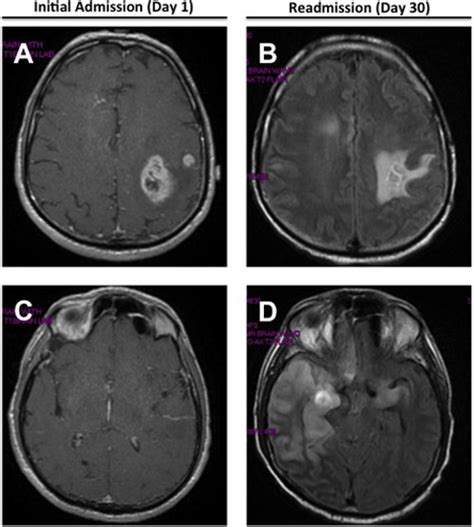

Herpes Simplex Virus (HSV-1) Encephalitis Mimicking Glioblastoma: Case ...